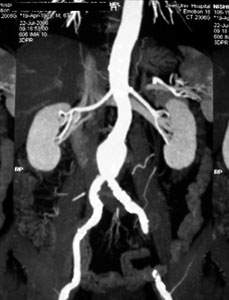

症例1

59歳 女性

【主 訴】

腹痛・体重減少(10kg)

【起始・経過】

平成15年7月より毎食後に腹痛出現。

平成18年5月他院腹部血管造影にて腹部動脈閉塞を認めたが、加療されず。

7月当院受診。

【既往歴】

41歳 子宮筋腫 → 手術

高血圧(+) 糖尿病(−) 喫煙歴(−)

【治療計画】

SMA PTA/stent(Brachial approach)

腹部血管造影検査